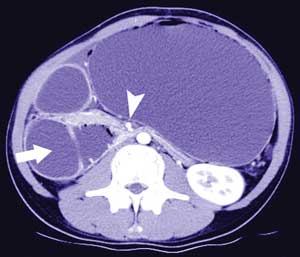

A 17-year-old man with a slim build presented with recurrent postprandial epigastric fullness and bilious vomiting. He was acutely unwell. An abdominal radiograph showed gastric and duodenal distension. Contrast computed tomography scans showed proximal duodenal dilatation (Box, A, arrow), with a triangular-shaped duodenum, extensive hepatic portal venous gas (Box, B, arrows), and a massively distended stomach.

Superior mesenteric artery syndrome with hepatic portal venous gas was diagnosed. This syndrome occurs when the fat pad between the superior mesenteric artery and its origin at the aorta is lost, causing a sharp, narrow angle at the aortomesentery junction. The third portion of the duodenum is compressed and becomes obstructed when passing through this angle.1 Hepatic portal venous gas can develop as a result of bowel ischaemia.